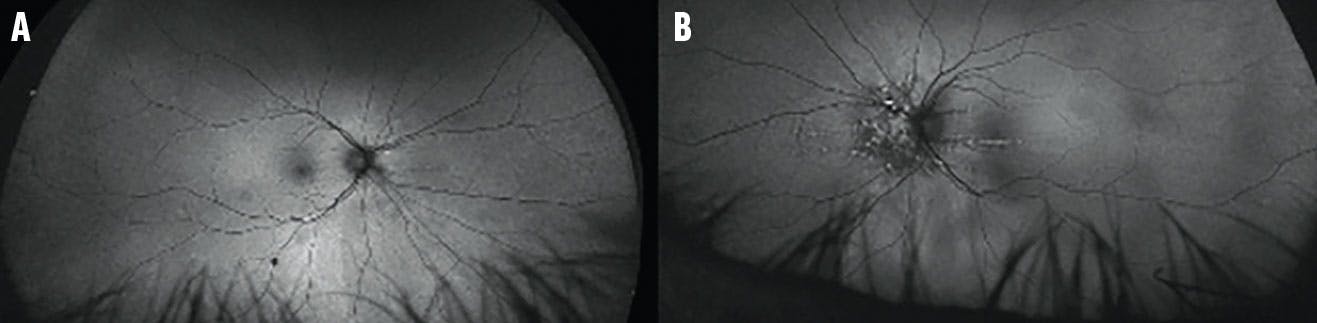

OCT revealed characteristic undulations of the RPE consistent with choroidal folds (Figure 3). Fluorescein angiography (FA) highlighted the choroidal folds in each eye (Figure 4). ICG did not reveal any choroidal masses (Figure 5), and a CT of the orbit was within normal limits. Blood workup was unremarkable.

<p>Figure 4. FA showed an increased stippled hyperfluorescence with late staining corresponding to an area of pigmentary disturbance in the right (A) and, more prominently, the left (B) eye.</p>

Figure 4. FA showed an increased stippled hyperfluorescence with late staining corresponding to an area of pigmentary disturbance in the right (A) and, more prominently, the left (B) eye.